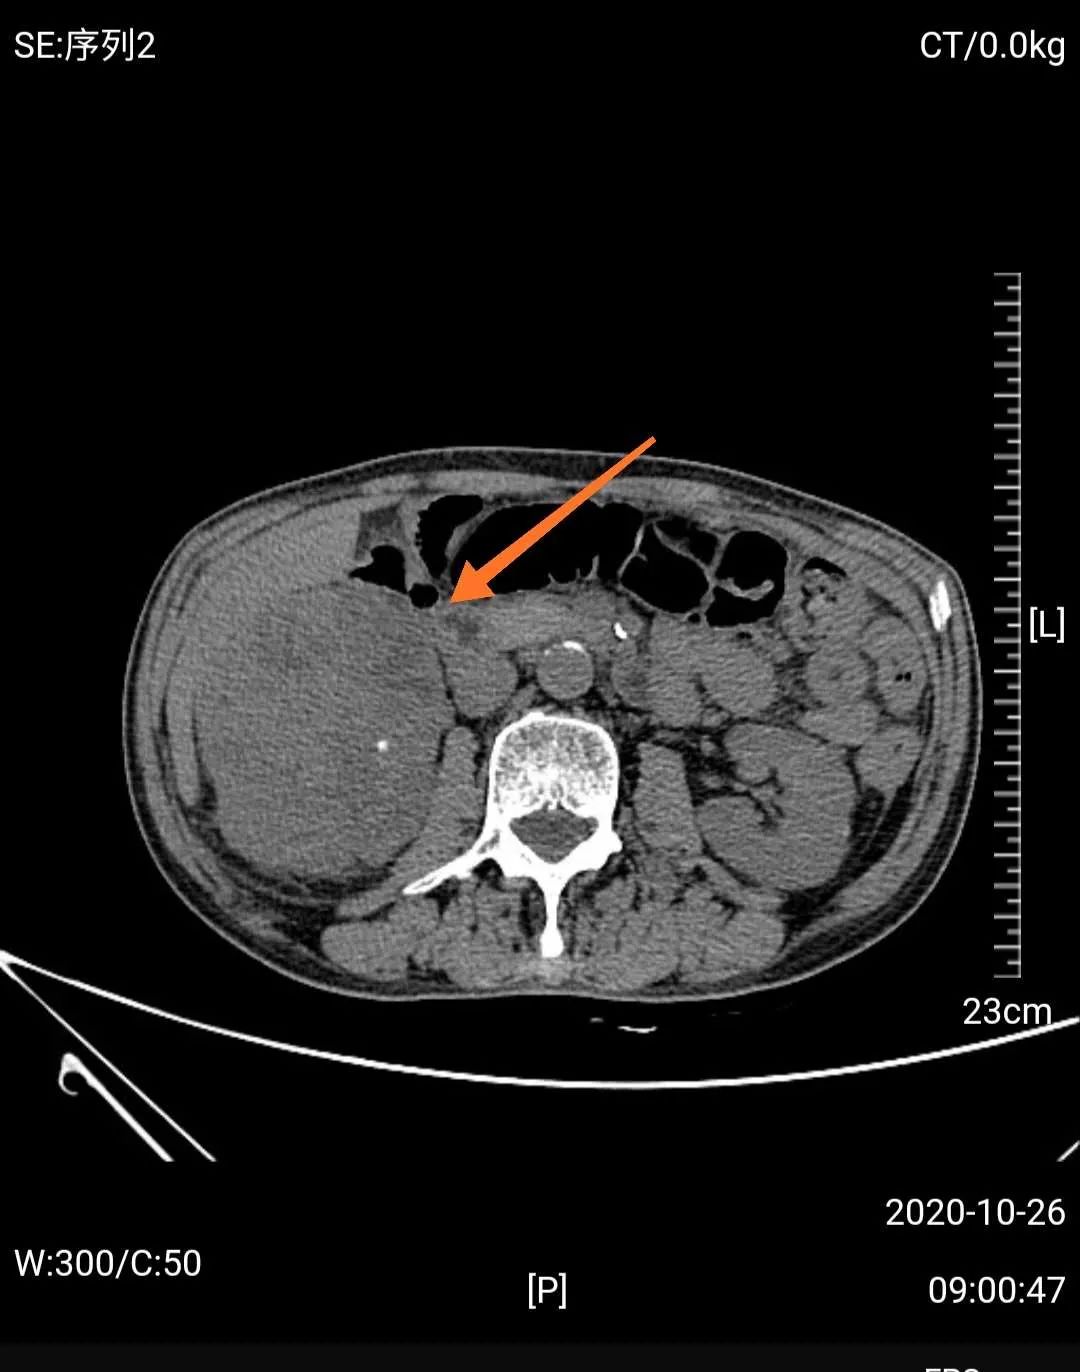

然而,门诊泌尿系超声检查发现,梁爷爷除了前列腺增生外,还有一个可怕的问题——右肾巨大肿瘤,考虑右肾癌可能性大。

经MDT团队研究,影像学团队分析认为老人诊断右肾癌相对明确,手术治疗是首选方案;心血管及肺病科团队认为老人虽然年龄大,高血压病史,但血压控制较好,心肺功能评估认为手术风险属于轻度;肿瘤科认为患者手术指征很明确,目前一般情况好,预期寿命长,内科治疗效果不及外科手术;中医治疗可以在外科手术后辅助,不能仅靠中医治疗。泌尿外科团队认为患者诊断考虑右肾癌,且左肾功能正常,右肾肿瘤巨大,建议根治性手术切除,考虑老人年纪大,开放手术创伤大,出血多,建议采用3D腹腔镜微创治疗。